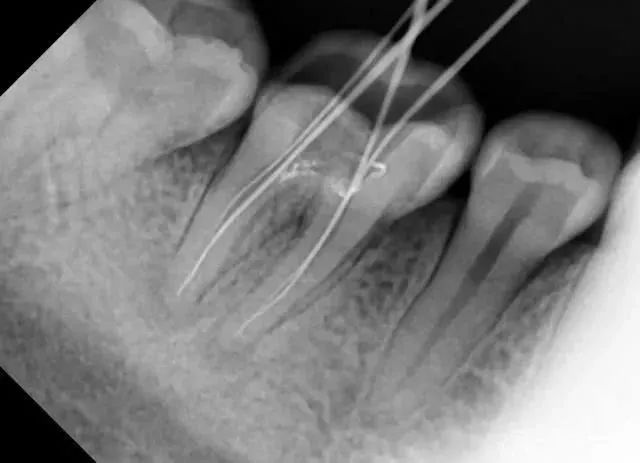

拍一张根尖片(小牙片)的辐射剂量等于一次吃下10根香蕉

拍一张小牙片=吃10根香蕉